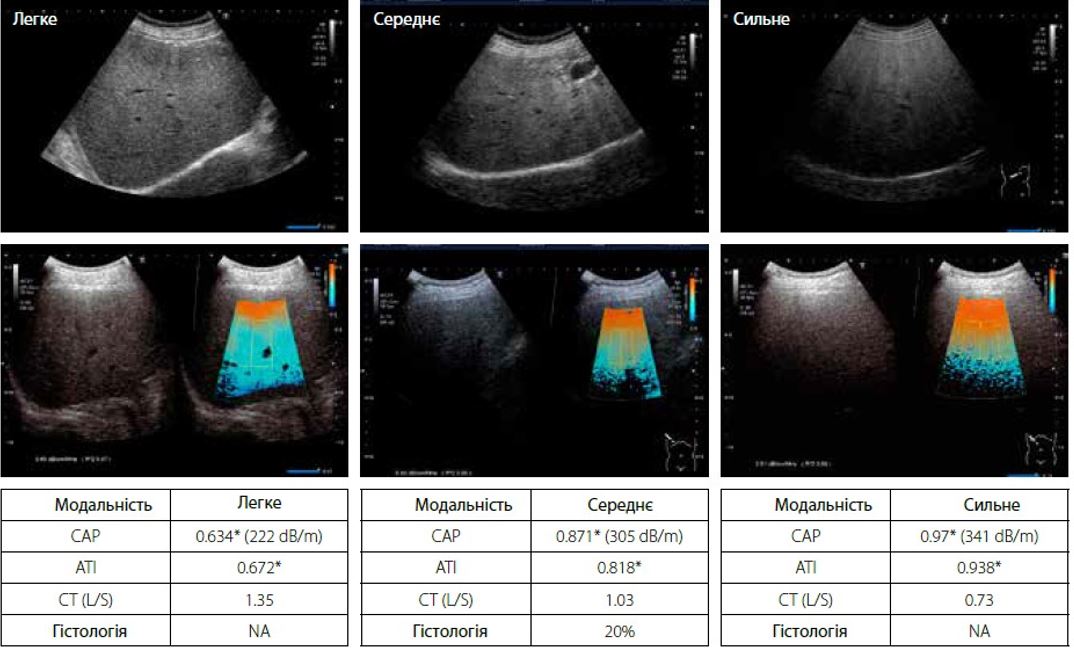

На малюнку 5 показано порівняння показників ATI та CAP та КТ при легкому, середньому та важкому ожирінні печінки. Відповідно до наявних даних в літературі, у пацієнта діагностують жирову дистрофію печінки, коли коефіцієнт ослаблення печінки до селезінки (L/S) на КТ становить менше 1,0 або 1,1; а вміст жиру в печінці більше 30%. ATI та CAP демонструють чудову кореляцію зі співвідношенням на КТ L/S.

* в dB/cm/MHz. Середнє значення після 10 вимірів.

Малюнок 5 Діагностика стеатозу за допомогою АТІ, САР та СТ L/S: співвідношення при легкому, середньому та сильному ожирінні печінки

При дослідженні кореляції між CAP та ATI з гістопатологією, CAP має більшу варіативність при кількісній оцінці тяжкого ожиріння печінки. Навпаки, ATI демонструє меншу варіативність і може діагностувати дуже легкий жировий гепатоз печінки (стеатоз < 10%, гістологія). Для гістологічного стеатозу ступінь жирової дистрофії печінки класифікується як нормальний (<10%), легкий (10-33%), помірний (33-66%) і важкий (>66%) відповідно. На основі посібника з діагностики NASH/NAFLD (2015) Японського товариства гастроентерології важливо діагностувати дуже легкий стеатоз у 5-10% для раннього лікування пацієнтів. При ранньому виявленні дуже легкого стеатозу пацієнт може без проблем позбутися ожиріння печінки за допомогою фізичних вправ і дієтотерапії.

Також оцінювали кореляцію між співвідношенням КТ L/S і ATI. На КТ три досліджувані ділянки діаметром 2 см були розміщені на печінці та селезінці відповідно, щоб отримати середнє співвідношення L/S. Ожиріння печінки діагностується, коли L/S <1,0. В той же час, ATI і CAP продемонстрували хорошу кореляцію зі співвідношенням КТ L/S, і особливо ATI демонструє меншу варіативність та більш стабільний результат. При оцінці 57 випадків із співвідношенням L/S >1,0 у 10 (18%) випадках згодом було діагностовано жирову дистрофію печінки з класифікацією B-режиму, що означає, що КТ може не помітити жирову печінку.